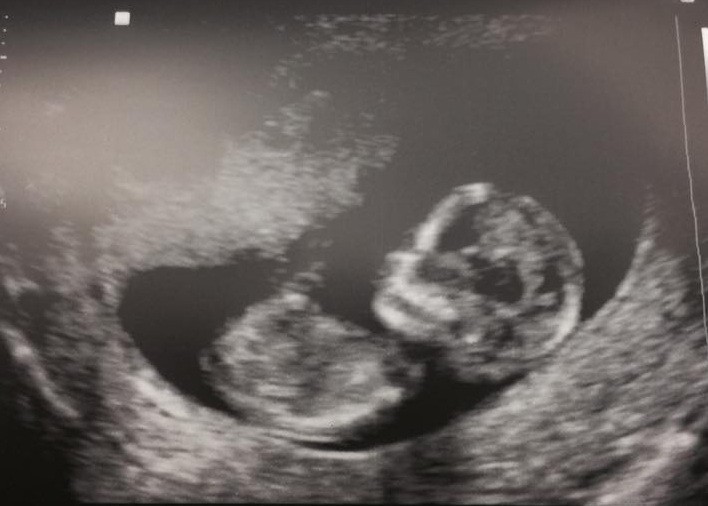

David Faustino, actorul care l-a interpretat pe Bud, mezinul familiei Bundy, a facut marele anunt: va deveni tatic. „Da, ea este însărcinată, iar eu o susţin. Va fi o fată, aşa că există şi nebunie şi emoţie”, a declarat David Faustino.

Actorul si iubita sa, Lindsay Bronson, vor deveni parintii unei fetite, la sfarsitul acestui an. Se pare ca numele pe care l-au ales pentru micuta lor e Eva.